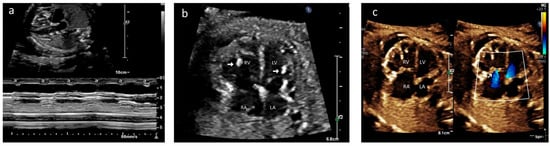

A female baby was delivered at 32 + 4 weeks of gestation with a birth weight of 1390 g and an APGAR score of 5, 9. The neonate was intubated and started on an isoprenaline infusion. CHB was confirmed by postnatal electrocardiogram (Figure 2), and echocardiography showed mild to moderate TR with no evidence of MR, and the atrioventricular valves appeared to be structurally normal (Figure 3a,b/Videos S3 and S4). There was hyperechogenicity on both ventricular myocardial walls, papillary muscles, and chordae. Cardiac function was normal (Figure 3c/Video S5). There was minimal pericardial effusion and no pleural effusion. After stabilization of the neonate, temporary epicardial pacing wires were inserted with VVI pacing mode on day two of life due to bradycardia. The neonate was extubated to room air on day 21 of life, and weekly follow-up echocardiograms showed stable cardiac function.

Figure 3.

Case A: (a) Postnatal echocardiogram—four-chamber view showing normal mitral and tricuspid valves. Hyperechoic papillary muscles (yellow arrow) were noted. RA—right atrium, LA—left atrium, RV—right ventricle, LV—left ventricle. (b) Immediate postnatal echocardiogram, long axis view, showing no regurgitation of the mitral valve. Ao—Aorta. (c) Postnatal echocardiogram, short axis at the level just below the mitral valve, showing hyperechoic papillary muscles in the left (bottom) and right (top) ventricles (white arrow).

A 35-year-old G2P1 with no prior history of autoimmune disease was referred to our center at 20 + 4 weeks of gestation for fetal hydrops and bradycardia. CHB was detected in fetal echocardiography with an atrial rate of 112 bpm and a ventricular rate of 62 bpm (Figure 5a). Mild to moderate TR was present without MR. Biventricular hyperechogenicity of the papillary muscles and endocardium was noted with good coaptation of the valve leaflets (Figure 5b/Video S12). Small pericardial and pleural effusions were also noted. She was extensively investigated for hydrops, and her anti-Ro antibody titers were strongly positive with negative anti-La titers. She declined medical therapy and had her pregnancy terminated.

Figure 5.

Case B: (a) M-mode echocardiogram showing atrioventricular dissociation in the fetus. A—atrial contractions; V—ventricular contractions. (b) Echocardiogram, four-chamber view—hyperechoic papillary muscle (white arrow in RV and LV).